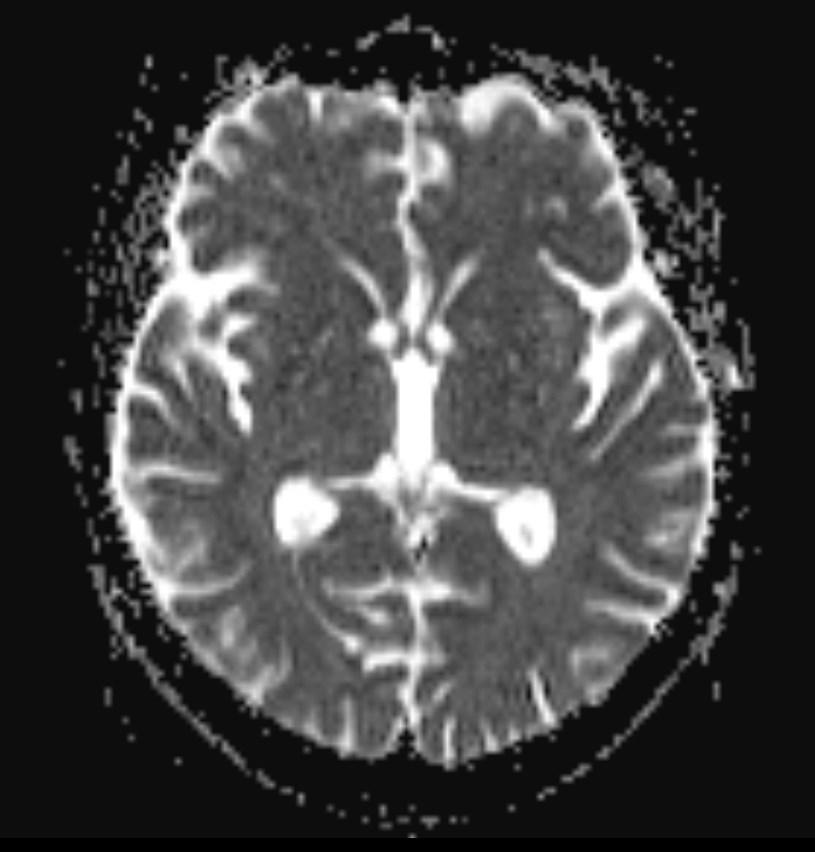

MRI images revealed hyperintensities in the periaqueductal region and the medial thalami.

T2/FLAIR: symmetrically increased signal intensity in the mamillary bodies, dorsomedial thalami, tectal plate, periaqueductal area, and around the third ventricle.